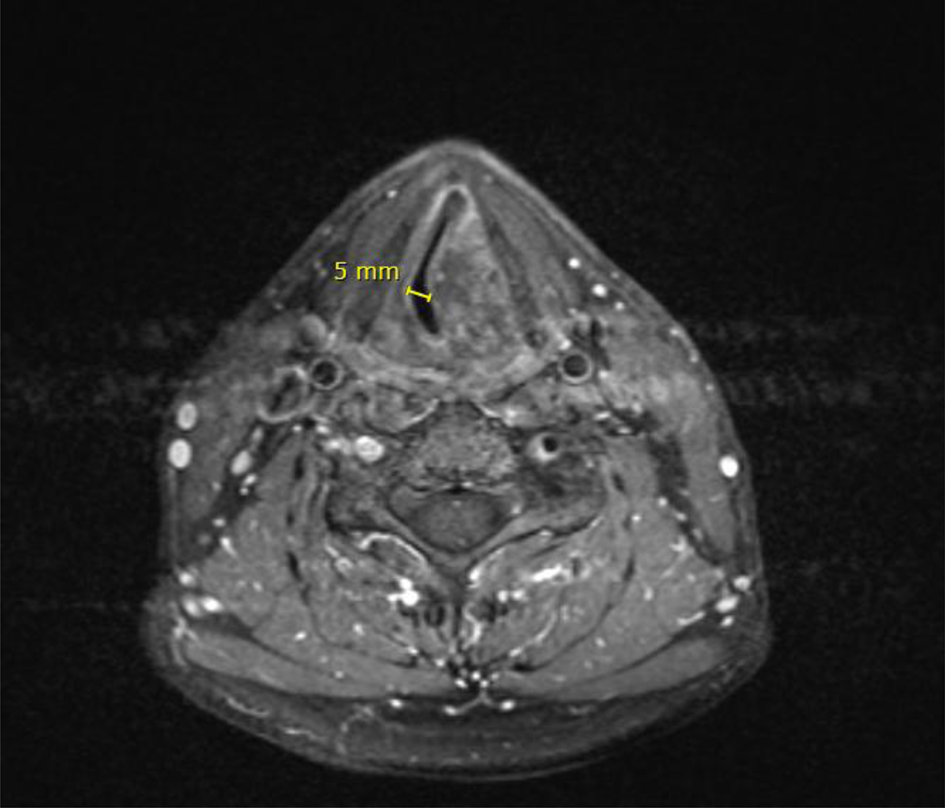

A 49-year-old otherwise healthy male teacher presented to a general hospital with hoarseness and stridor that had slowly progressed over 12 months. On digital flexible laryngoscopy, a supraglottic submucosal mass was seen at the site of the left arytenoid (Figure 2). A magnetic resonance imaging scan showed enlarged left arytenoid cartilage with calcifications, indicative of a chondral tumour (Figure 3).

Fig. 3. Axial magnetic resonance imaging scan showing a maximum airway diameter of under 5 mm.

Because of the fixed intralaryngeal obstruction with a diameter of less than 5 mm, a Tritube was used for intubation. This small tube could just be passed through the narrowed airway with some resistance. There were no complications during or after intubation.